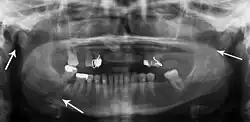

Panoramic radiography

Panoramic radiographs are tomograms where the mandible is in the focal trough and show a flat image of the mandible. Because the curve of the mandible appears in a 2-dimensional image, fractures are easier to spot leading to an accuracy similar to CT except in the condyle region. In addition, broken, missing or malaligned teeth can often be appreciated on a panoramic image which is frequently lost in plain films. Medial/lateral displacement of the fracture segments and especially the condyle are difficult to gauge so the view is sometimes augmented with plain film radiography or computed tomography for more complex mandible fractures.

Research has shown that panoramic radiography is similar to computed tomography in its diagnostic accuracy for mandible fractures and both are more accurate than plain film radiograph.[12] The indications to use CT for mandible fracture vary by region, but it does not seem to add to diagnosis or treatment planning except for comminuted or avulsive type fractures,[13] although, there is better clinician agreement on the location and absence of fractures with CT compared to panoramic radiography.[14]

Panoramic radiograph of a simple mandible fracture of the right mandibular body, minimally displaced. Note that the teeth to the left of the fracture do not touch